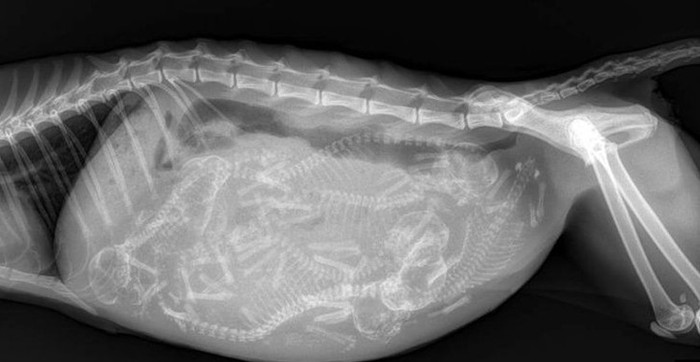

Anak-anak kucing yang masih di dalam perut sang induk. (Foto: Brightside)